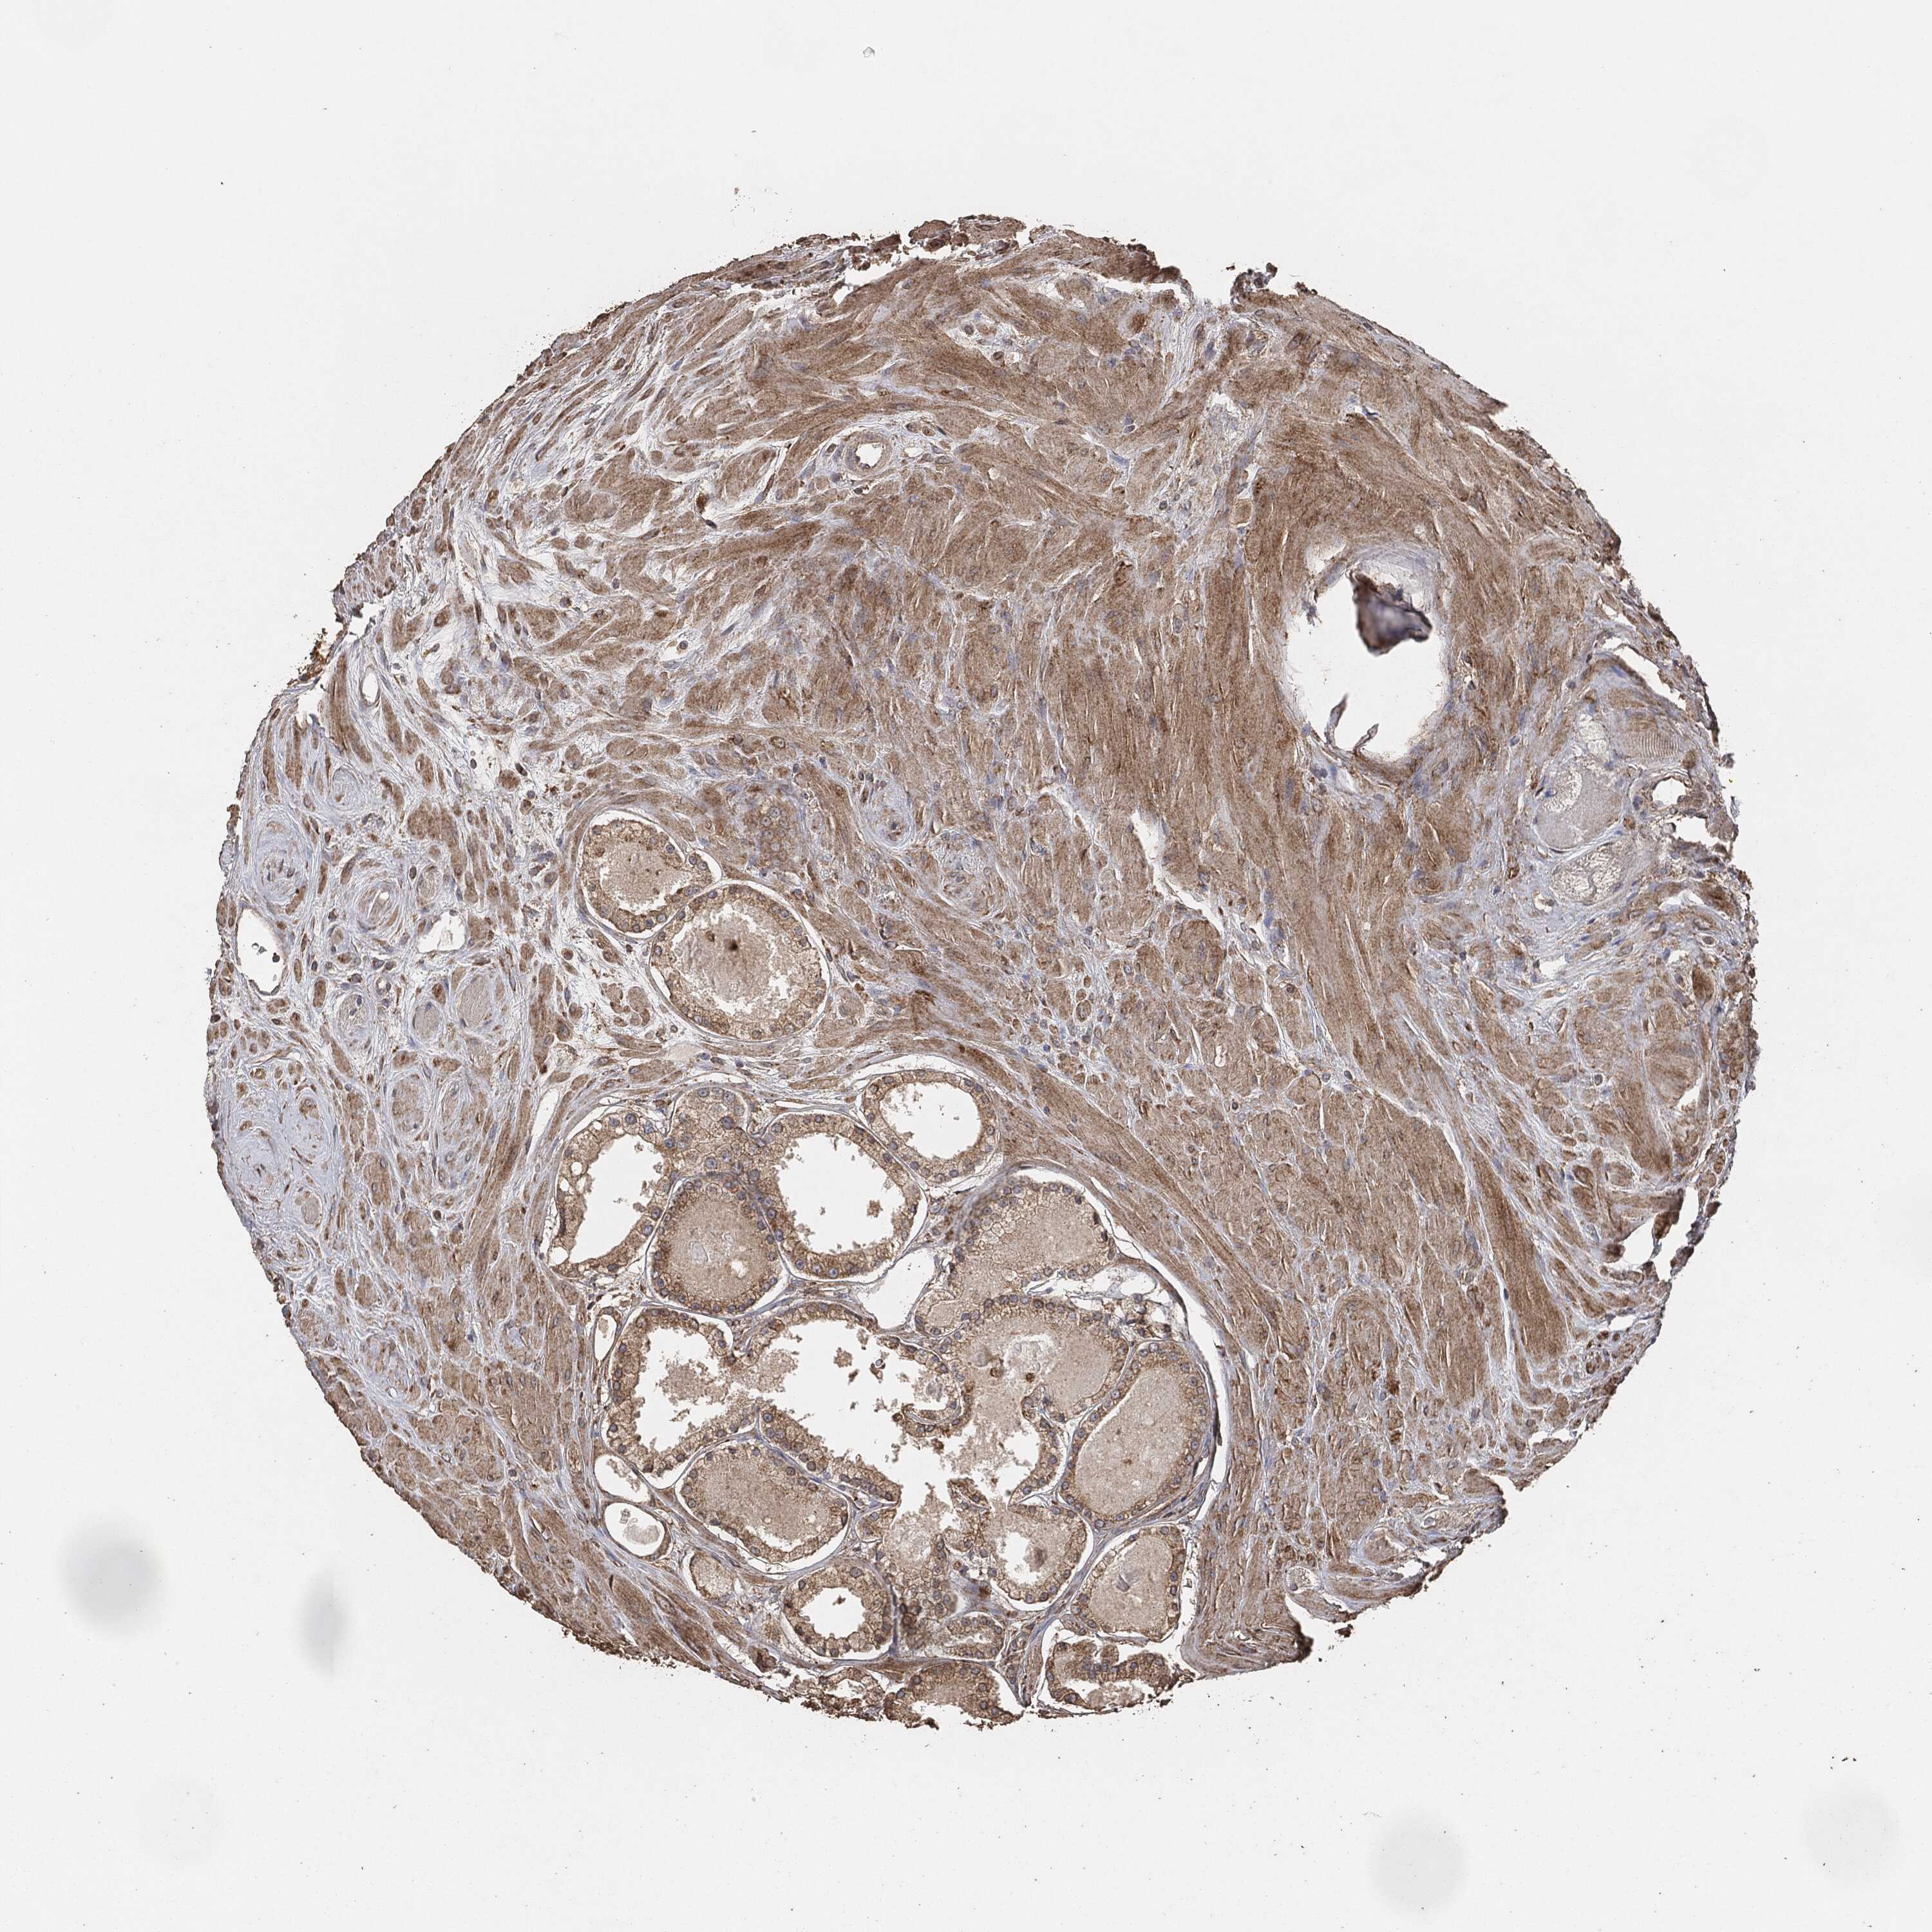

PROSTATE CANCER - Protein expressioni

A mouse-over function shows sample information and annotation data. Click on an image to view it in a full screen mode. Samples can be filtered based on level of antibody staining by selecting one or several of the following categories: high, medium, low and not detected. The assay and annotation is described here.

Note that samples used for immunohistochemistry by the Human Protein Atlas do not correspond to samples in the TCGA dataset.

Antibody stainingi

Antibody staining in the annotated cell types in the current human tissue is reported as not detected, low, medium, or high, based on conventional immunohistochemistry profiling in selected tissues. This score is based on the combination of the staining intensity and fraction of stained cells.

Each image is clickable and will lead to virtual microscopy that enables deeper exploration of all samples and also displays staining intensity scores, fraction scores and subcellular localization as well as patient and tissue information for each sample.

Adenocarcinoma, Medium grade

Adenocarcinoma, Low grade

Adenocarcinoma, High grade

Adenocarcinoma, NOS